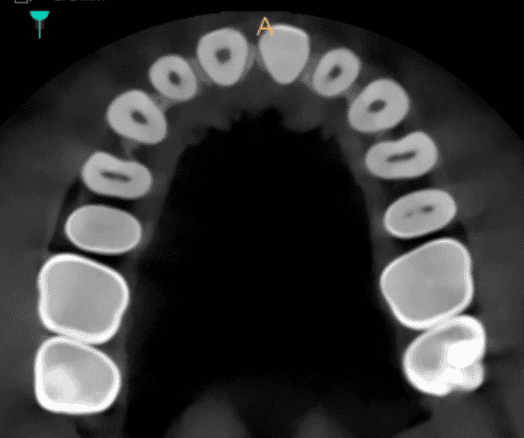

Sclerosis - CBCT scans